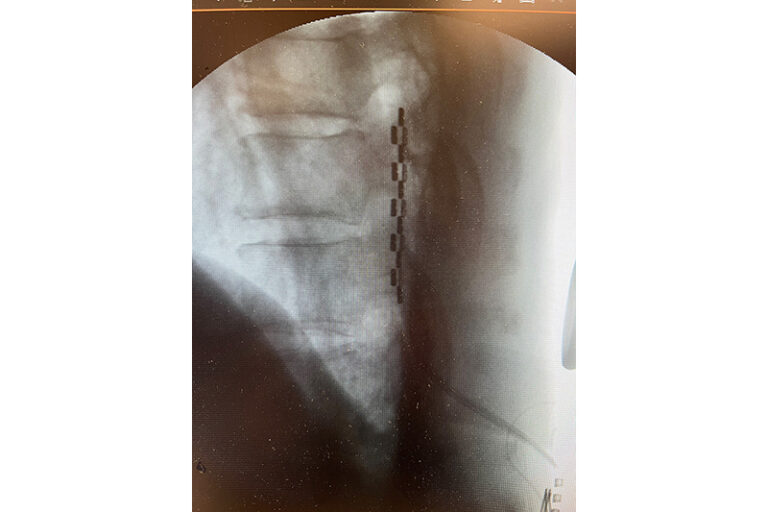

圖:經皮下穿刺放入電極(深黑色點)到脊髓背部的硬膜外空間,X光掃描確保電極放在理想位置。(相片由醫生提供)